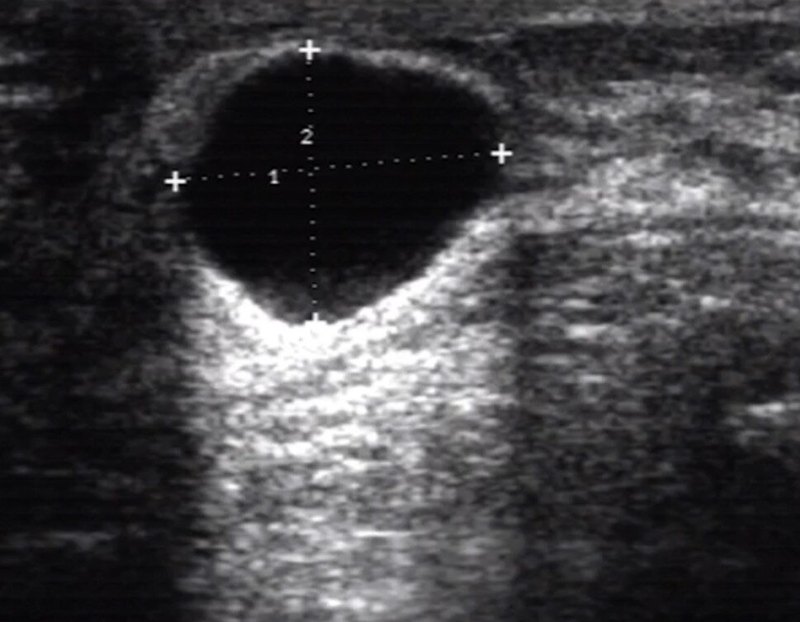

乳腺囊腫的治療方法需要分不同情況采取不同的處理方法。乳腺囊腫在女性乳腺彩超檢查時(shí)會(huì)經(jīng)常遇到,所謂囊腫,通俗講,就是“一包水”。它的具體發(fā)病原因尚未完全明確,但現(xiàn)有證據(jù)證實(shí)乳腺囊腫的發(fā)生與體內(nèi)雌激素水平相關(guān)。乳腺增生本身也會(huì)出現(xiàn)一些小的囊腫樣改變,因此乳腺增生也有說(shuō)法稱(chēng)之為乳腺囊性增生癥。一些哺乳期后的病人,可能因?yàn)闅埓嫒橹琶诓煌〞扯鴮?dǎo)致積乳囊腫。乳腺囊性病變少有惡性可能,但臨床需要排除一些乳腺惡性腫瘤伴隨局部壞死導(dǎo)致彩超影像學(xué)出現(xiàn)局部囊性病變的情況。單純?nèi)橄倌夷[一般不會(huì)導(dǎo)致乳房疼痛等伴隨癥狀。小的乳腺囊腫一般不需要處理,定期復(fù)查即可,如果囊腫較大,則可以行彩超指引下針穿抽吸內(nèi)容物囊液,之后局部加壓包扎一周左右進(jìn)行治療。近年來(lái)有醫(yī)生將乳腺真空輔助旋切系統(tǒng)應(yīng)用于較大且多發(fā)的乳腺囊腫治療,手術(shù)方法簡(jiǎn)單易行,副作用小,可以在門(mén)診進(jìn)行治療。積乳囊腫如果較大,一般也建議手術(shù)切除或真空輔助旋切手術(shù)治療。

臨床工作中,乳腺囊腫經(jīng)常在乳腺超聲檢查時(shí)發(fā)現(xiàn),一般超聲醫(yī)生都會(huì)用“水泡泡”來(lái)形容“乳腺囊腫”,那這個(gè)“水泡泡”真的不用管嗎?一、“乳腺囊腫”是怎么形成的??“乳腺囊腫”是指乳房?jī)?nèi)形成的圓形或橢圓形、充滿(mǎn)液體的囊狀包塊,主要與局部乳腺導(dǎo)管堵塞有關(guān),在正常人群中發(fā)病率較高,約5%。二、“乳腺囊腫”是良性的嗎?“乳腺囊腫”絕大多數(shù)都是良性的,但當(dāng)超聲發(fā)現(xiàn)為復(fù)雜性囊腫是仍要引起警惕,另外一些特殊的、良性的“乳腺囊腫”也可能需要處理。三、特殊的“乳腺囊腫”有什么?1)持續(xù)增大的囊腫:乳腺囊腫為多發(fā)、體積較小,多<1.5cm;若囊腫體積較大并持續(xù)性增大時(shí),不能排除體積較小、不易被探查到的導(dǎo)管內(nèi)乳頭狀瘤附著囊壁上。2)突然增大伴疼痛的囊腫:這種情況下往往是囊腫內(nèi)發(fā)生了感染引起的,您可在乳腺超聲檢查排除惡性腫塊的前提下,服用抗生素治療炎癥。3)積乳囊腫:即我們通俗說(shuō)的“奶結(jié)”,通常這種囊腫在哺乳結(jié)束后會(huì)慢慢縮小,若哺乳結(jié)束后不縮小或縮小后停滯不小,也需要予以治療。如下圖,我畫(huà)了常見(jiàn)的乳腺囊腫的示意圖及相應(yīng)處理原則,以供大家參考。

乳腺囊腫是什么?乳腺囊腫是指乳房?jī)?nèi)形成的邊界清晰、圓形或橢圓形、充滿(mǎn)液體的囊狀包塊,類(lèi)似一個(gè)“水球”。乳腺囊腫里面的液體可能是由囊壁上的細(xì)胞分泌出來(lái)的,也有可能是乳汁潴留形成的,也有可能是炎癥導(dǎo)致的。囊腫可單發(fā)也可多發(fā),觸感一般較軟,少數(shù)質(zhì)地較硬。02乳腺囊腫需要手術(shù)治療嗎?乳腺囊腫通常無(wú)需治療,以隨訪觀察為主。如果囊腫直徑較大(>3厘米),可以考慮做囊液穿刺抽吸治療。如患者有明顯不適,或者乳腺囊腫內(nèi)回聲不均勻、鈣化,或者囊腫較大合并其他病變時(shí)才考慮進(jìn)行手術(shù)治療。目前多采用真空輔助乳腺微創(chuàng)旋切術(shù),又稱(chēng)“麥默通”手術(shù),其特點(diǎn)是切口微小、隱蔽、手術(shù)時(shí)間短、出血少、愈合快、術(shù)后乳房塌陷發(fā)生率低等等。微創(chuàng)手術(shù)主要適用于:1.單發(fā)囊腫、內(nèi)部回聲不均且直徑大于1cm者;2.多發(fā)囊腫伴有嚴(yán)重?zé)o規(guī)律疼痛或觸診局部腺體增厚并經(jīng)3個(gè)月藥物治療無(wú)效者;3.囊腫與低回聲結(jié)節(jié)、乳管擴(kuò)張等病灶并存者;4.病變周?chē)袤w組織彩超下回聲雜亂或血供豐富者;5.有乳腺癌發(fā)生高風(fēng)險(xiǎn)者。03乳腺囊腫可以口服藥物治療嗎?乳腺囊腫目前尚無(wú)確切的藥物治療方案,使用避孕藥(口服避孕藥)調(diào)節(jié)月經(jīng)周期可能有助于減少乳腺囊腫的復(fù)發(fā)。避孕藥或其他激素(如他莫昔芬)可能存在明顯的副作用,通常僅推薦用于癥狀嚴(yán)重的女性。在絕經(jīng)后停止激素治療也可能有助于預(yù)防乳腺囊腫。如果是積乳囊腫伴發(fā)感染,可以使用抗生素治療。

??并非所有的乳腺囊腫都是良性的乳腺囊性病變常見(jiàn)以下幾種類(lèi)型:?單純囊腫型:囊腫、導(dǎo)管局部擴(kuò)張及纖維囊性變等良性病變?復(fù)雜囊腫型:膿腫、積乳囊腫、導(dǎo)管局部擴(kuò)張的、纖維囊性病變、脂肪壞死等?簇狀微小囊腫型:纖維囊性病變等?復(fù)合囊腫型(囊壁或分隔增厚型、囊內(nèi)型、囊性為主型、實(shí)性為主型)各種類(lèi)型的乳腺囊性病變,良惡性概率是多大呢??單純囊腫型常為良性病灶,以隨訪為主?復(fù)雜囊腫型惡變率小于1.4%,平均0.4%?簇狀微小囊腫型以良性為主?復(fù)合囊腫型的惡變率約為22%~31%所以,如果您發(fā)現(xiàn)了乳腺?gòu)?fù)合囊腫,需要警惕惡性可能。必要時(shí)需要進(jìn)行手術(shù)活檢,明確病理診斷。如果您有關(guān)于乳腺方面的問(wèn)題,歡迎隨時(shí)向我咨詢(xún)